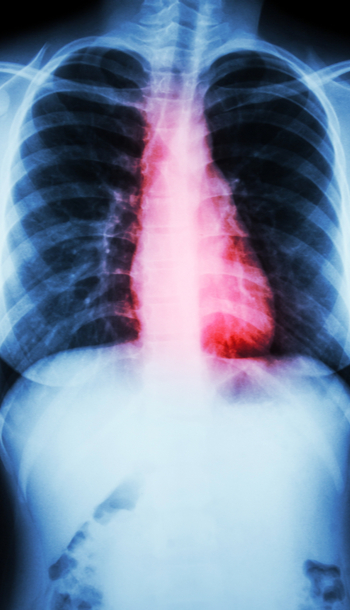

Plan de cuidados: EPOC

En el siguiente caso clínico sobre el Plan de cuidados del paciente con EPOC se mostrarán los cuidados de enfermería a seguir para mejorar y prevenir posibles complicaciones de salud de estos pacientes. Las autoras del caso clínico son Ana Isabel Terriza Torres y Mª...